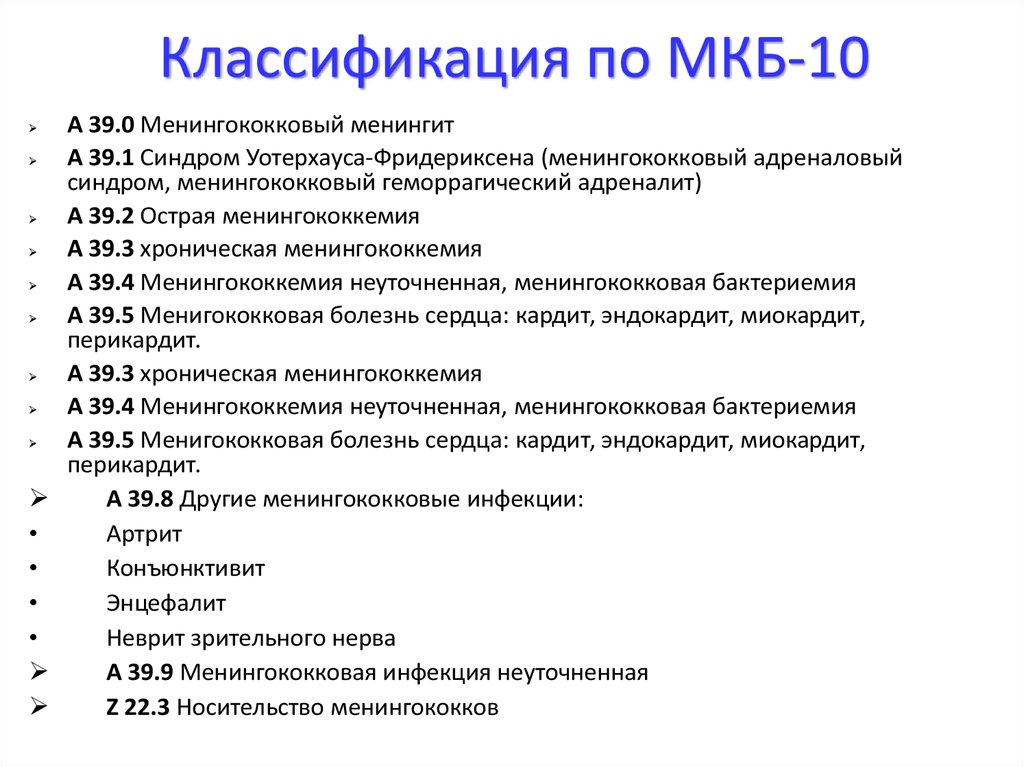

Код мкб 10 атерома головы

Код мкб 10 атерома головы 109 фото